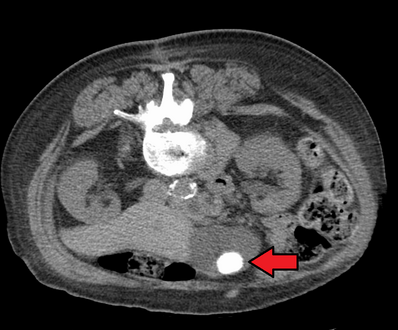

صور طبقية محوسبة لحصوات المرارة.

عادة ما يتأكد التشخيص عن طريق التصوير بالموجات الصوتية على البطن. تقنيات التصوير الأخرى المستخدمة هي ERCP وMRCP. قد يتم الكشف عن مضاعفات الحصوة في تحاليل الدم.[2]

في الموجات فوق الصوتية على البطن، عادةً ما يكون لحصوات المرارة الغارقة ظل صوتي خلفي. في حصوات المرارة العائمة، يُشاهد صدى الصدى (أو قطعة أثرية على شكل ذيل المذنب) بدلاً من ذلك في حالة سريرية تسمى الورم العضلي الغدي تكون هناك علامة أخرى هي ثالوث جدار الصدى والظل (WES) (أو الظل المزدوج القوس) والذي يعد أيضًا من سمات حصوات المرارة.[37]